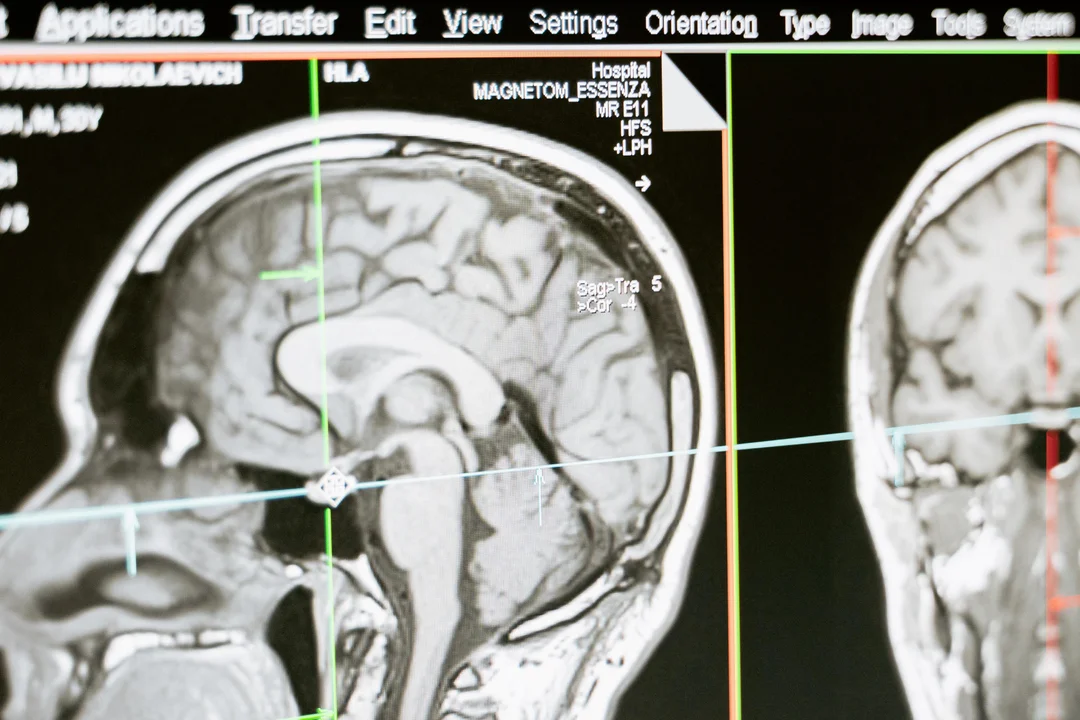

Gwałtownie rośnie liczba niedokrwiennych udarów mózgu. Będzie ich jeszcze więcej. Sprawdź, czy jesteś w grupie ryzyka - Zdjęcie główne

Autor: pexels | Opis: Średnio co 6,5 minuty ktoś w Polsce doznaje udaru mózgu. To pierwsza przyczyna trwałej niepełnosprawności wśród dorosłych Polaków.